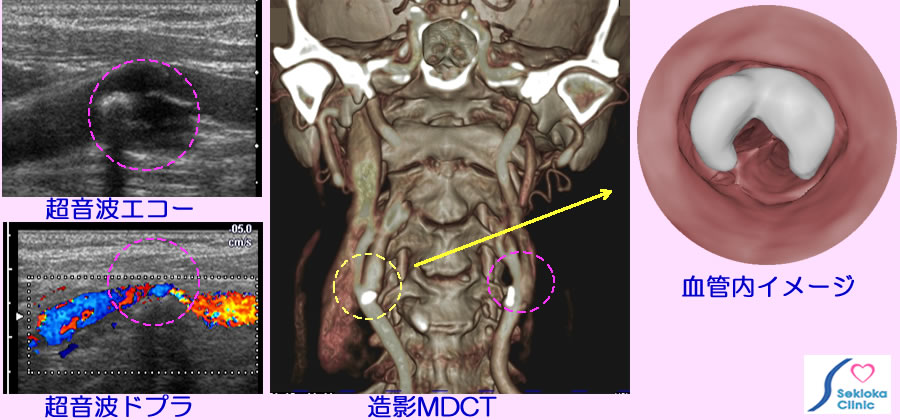

超音波エコーは簡便で容易な検査、血管を詳細、広範囲に検査するにはMDCT、MRI。添付画像の波線円内が頸動脈の狭窄部位。左上段の超音波エコーで動脈硬化病変(アテローム)と血管狭窄を認め、左下段はドプラ法で血管内の血流を画像化。中央の画像は造影MDCT 波線円内の狭窄部位に白く描画されているのは石灰化(動脈硬化)病変です。黄色波線内の血管内イメージを3次元MDCT画像から作成した画像を右側に示しています。白く描出された石灰化病変で血管内腔は狭くなり、その奥に内・外頸動脈の分岐部が見えます。容易かつ明瞭に血管内の状態を理解できます。